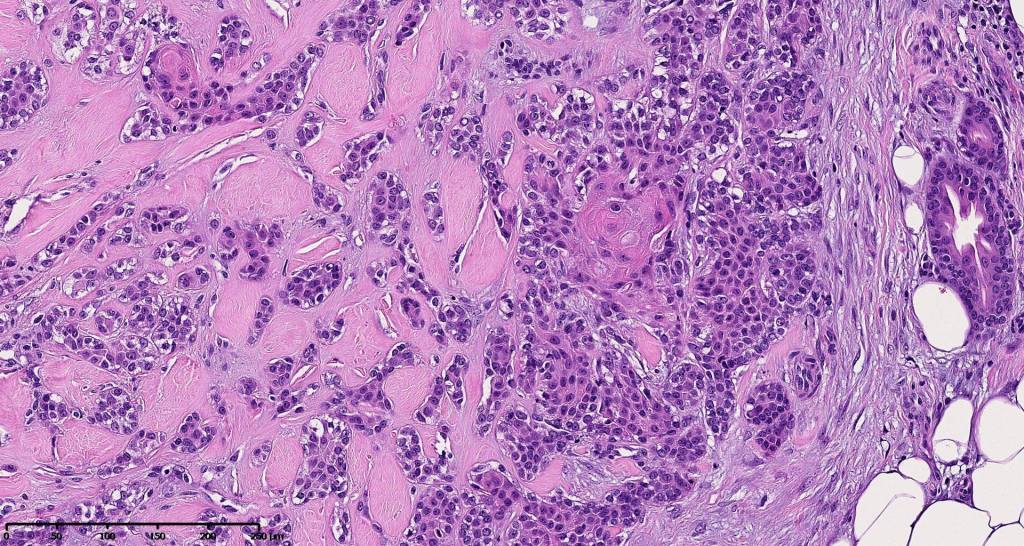

•Well circumscribed unencapsulated, nodular/multinodular silhouette composed of an admixture of epithelial & mesenchymal elements

•Mixed epithelial component including nests & cords of epithelium with abundant, eosinophilic cytoplasm & small vesicular nuclei

•Clear cell change

•Glandular differentiation sometimes showing apocrine differentiation

•Plasmacytoid myoepithelial cells; clear cell change

•Follicular & sebaceous differentiation

•Keratocysts & squamous foci

•Chondroid foci